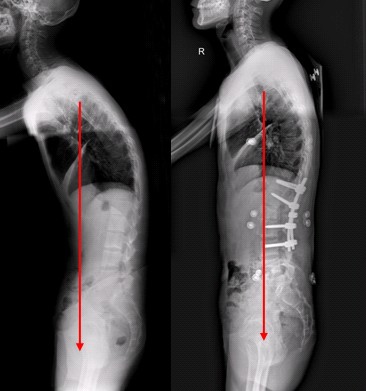

强直性脊柱炎是一种对人体伤害很大的骨科类疾病,而且是一种慢发性的疾病,如果不及时的治疗,就会扩张以至于导致一系列的并发症。我们知道强直性脊柱炎的治疗也是一大难题,那么手术治疗强直性脊柱炎效果怎么样?我们请 贵阳风湿病医院 的专家来为大家介绍吧...[详细] 2016-01-05

我们知道许多强直性脊柱炎患者在确证之后多问中晚期了,那么强直性脊柱炎到了晚期应该怎么治?强直性脊柱炎是种慢性风湿病,发病较缓慢,而且症状不明显,这个时候强直性脊柱炎在不好好治疗就可能致残,下面我们来看一下 AS到了晚期应该怎么治疗 。 运动疗法-...[详细] 2015-12-31